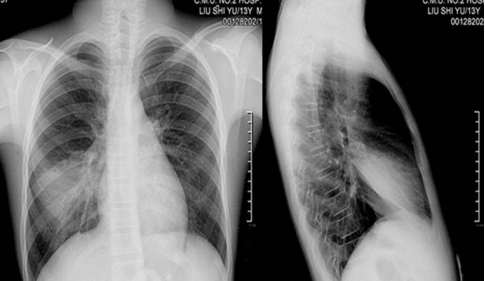

吃了第三疗程的时候就能下地活动了,各种症状都没了。在6个月后CT显示肺部无纤维化征象,肺功能都恢复了正常。医生对于检查结果也颇感意外,说从来没有看到间质性肺炎、慢阻肺竟然能恢复的这么好。我自己真的不敢相信我这么严重的病情竟然就治疗好了。十几年过去了,在这期间就断断续续的在袁主任那边调理下身体,现状态良好,正常外出活动旅游。我能继续陪伴女儿了,女儿别提多高兴了。她还建议我把自己的经历写下来分享给更多的人,让他们和我一样能安享晚年。

(这是治疗恢复后检查的)